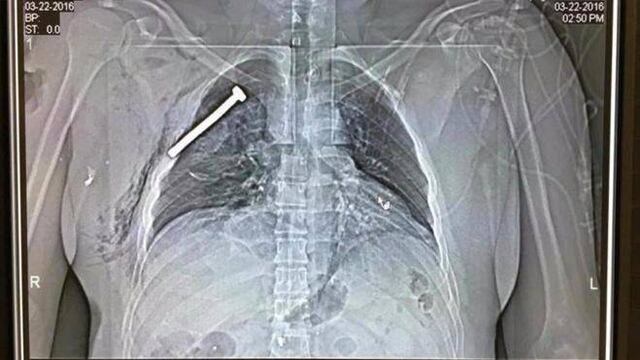

Los dos terroristas suicidas que provocaron los atentados en el aeropuerto de Zaventem llevaban bombas escondidas en las maletas que desplazaban en carritos portaequipajes. De acuerdo con información de agencias, todo apunta a que habrían rellenado los explosivos con tornillos para causar el mayor daño posible cuando activaron los detonadores.

En la radiografía de una persona herida en el aeropuerto divulgada por el diario La Libre Belgique se puede observar un tornillo de tamaño considerable incrustado en uno de sus pulmones.

Un administrador del hospital universitario de Gasthuisberg de Lovaina, indicó que la mayoría de las víctimas que atendieron presentaban heridas que corroboran esa teoría. La mayoría de los heridos sufrió fracturas. Quemaduras y graves cortes provocados por objetos metálicos.